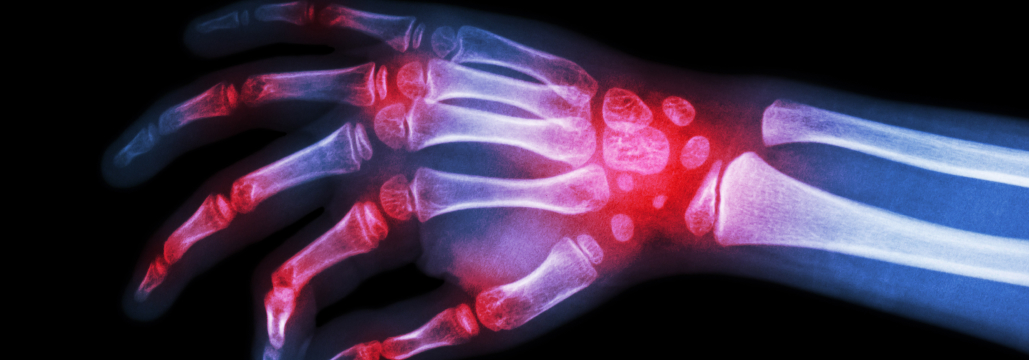

Jannat-Khahらは、 免疫チェックポイント阻害薬 (ICI、 ニボルマブ/ペムブロリズマブ/アテゾリズマブ) 治療を受けた66歳以上の転移性非小細胞肺癌 (mNSCLC) 患者2,732例を対象に、 関節リウマチ (RA) 併存が全生存期間 (OS) に及ぼす影響を後ろ向きコホート研究で検討した。 その結果、 RA併存の有無でOSに有意差は認められなかった (Kaplan-Meier生存曲線: log-rank p=0.08、 調整済みCox比例ハザードモデル: HR 0.92 [95%CI 0.78-1.09])。 男性、 併存疾患の多さ、 ICI導入前のステロイド投与量はOS低下と関連していたが、 ベースラインでデキサメタゾンを使用していた患者を除外した感度分析では、この関連は認められなかった。